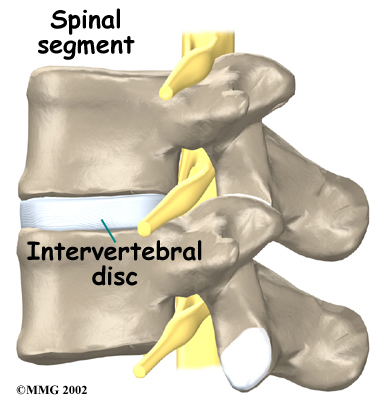

It is sometimes easier to understand how the spine works by looking at a spinal segment. A spinal segment consists of two vertebrae separated by an intervertebral disc, the nerves that leave the spinal cord at that level, and the small facet joints that link each level of the spinal column together.

The intervertebral discs normally work like shock absorbers. They protect the spine against the daily pull of gravity. They also cushion the spine during strenuous activities that put extensive pressure on the spine, such as jumping, running, and lifting.

An intervertebral disc is made up of two parts. The center, called the nucleus pulposus, is spongy and provides most of the disc's ability to absorb shock. The spongy center is also designed to transmit force and resist rotation. The nucleus pulposus is held in place by the annulus, which is found on the outside of the disc. The annulus is a series of strong ligamentous rings. Ligaments are strong connective tissues that attach bones to other bones. These ligaments form a criss-cross layer of protective tissue around the middle of the disc (the nucleus pulposus). The criss-cross formation is significant, as only half of the ligaments engage when the spine rotates to one side, while the ligaments on the opposite side remain stationary. The same activity occurs when the spine is rotated in a different direction. The criss-cross structure of the ligaments that make up the annulus provide maximum support, resistance, and flexibility of the spine.

There are also two facet joints—one on each side of the spine—that connect two stacked vertebrae in a spinal segment. Facet joints are located along the sides of the entire spine, from the neck down to the sacrum. The pattern and alignment of the facet joints in the lumbar region allow the spine to easily bend forward and backward. The anatomy of the lumbar spine also allows a certain degree of rotation, but not as much as the spinal segments in the cervical or thoracic spine. As the lumbar spine rotates, the facet joints squeeze together on one side and slightly expand on the other side to facilitate spinal movement.